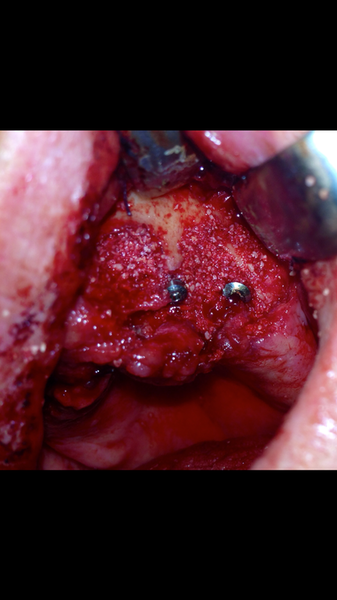

Impianti post-estrattivi complessi con innesto osseo